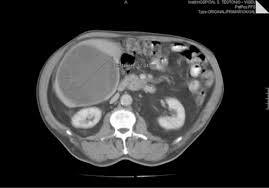

abscesso hepatico NA TC

(NEGOCIO QUE TEM LIQUIDO DENTRO) E EDEMA EM VOLTA, AS VEZES FICA MAIS CLARO NAS MARGENS

massa hipodensa bem definida com paredes/septos de reforço e edema periférico, como visto neste caso. O gás está presente em uma minoria de abscessos piogênicos.